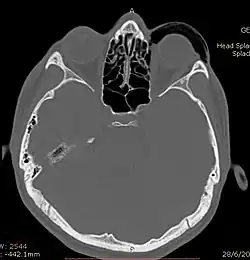

Woman with preorbital swelling in orbital emphysema shown in CT scans

CT scan taken from the transverse plane demonstrating orbital emphysema.[39]

Computed tomography is effective and sensitive in the diagnosis of orbital emphysema,[3][37] as it can confirm the anatomical location and size of air, bony defects, indentation of the eyeball, and the condition of the optic nerve, as well as the presence of any extraocular muscle entrapment and herniation of preorbital fat into the sinus cavities.[3][15][38] The location of the orbital emphysema is present near the site of the fracture.[1][3] The scans are usually taken along the transverse plane. Transverse images allow the evaluation of fractures in medial and lateral orbital walls. By reformatting these transverse images or taking coronal images, the examination of orbital floor and roof is permitted. Helical scanning is preferred as it has a lower imaging time and radiation dose comparing to conventional scanning, especially when reforming transverse helical scans into coronal images.[3] The staging of orbital emphysema can then be determined with visual acuity examination and ophthalmoscopy.[6] A disadvantage of using a CT scan is that when detecting air after orbital trauma, the presence of a wooden foreign object can give a false positive result of orbital emphysema. The wooden object can mimic the presence of orbital emphysema. Therefore, patients’ medical history is crucial in making the correct diagnosis.[3]